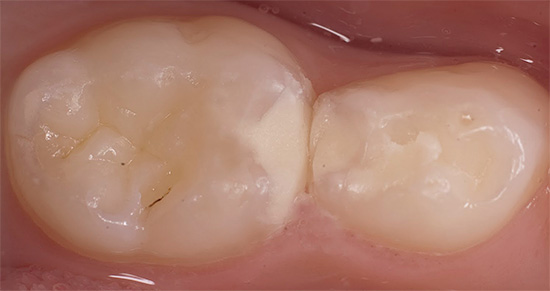

As clínicas modernas dão preferência a materiais de cura por luz funcionais e estéticos que se provaram no tratamento de cáries profundas. Eles são colocados em cavidades cariosas de qualquer classe, de uso conveniente, fácil e firmemente presos aos tecidos dos dentes e bastante duráveis com a execução exata dos detalhes técnicos da produção.

- E, finalmente, a formulação do selo, selecionado de acordo com as características da cavidade a ser preenchida.